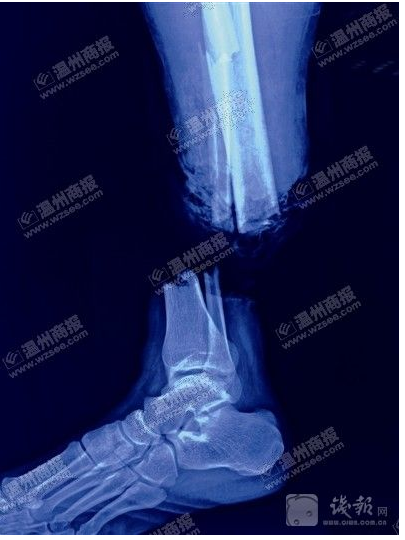

X光显示鲍成远右小腿完全被勒断。医院供图金鱼翻拍

刘斌告诉记者,在缆绳巨大作用力下,鲍成远右小腿伤口周围皮肤被挤压变形,近端皮肤缺损,胫骨粉碎性骨折,腓骨多段骨折。

手术过程中,他们对鲍成远伤口处一些挫烂后无生机、无活力的软组织进行剪除。然后,通过锁钉螺钉对骨折部位进行固定,接着,从身体其他部位移植肌腱、血管等,在显微镜下,对右小腿缺损的肌腱、血管等处进行缝接。经过10余小时手术,鲍成远的断腿终于成功接回。